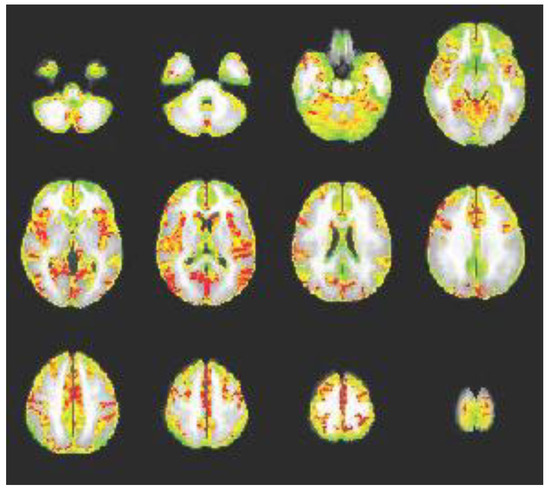

Another feasibility objective was to use individual rs-fMRI scans to produce a valid group-based motor connectivity map from the precentral gyrus (i.e., primary motor cortex) seed. In particular, the connectivity map should show graded patterns of activity rather than random pixelation. To produce this map, AFNI’s 3dDeconvolve tool was used. A general linear model (GLM) was applied to each participant’s co-registered functional images (ignoring censored values). The GLM analysis incorporated covariates accounting for linear, quadratic, cubic, and quartic drift and six motion parameters, as well as the seed (precentral gyrus) time series. AFNI’s 3dttest++ function was then used to produce seed-based connectivity maps. The validity of this map was judged qualitatively.

Group-Based Connectivity Map: The group connectivity map was deemed a valid connectivity map, as connectivity (red areas) can be observed between the precentral gyrus and multiple other brain areas that are associated with motor function: bilateral insula, superior parietal lobule, paracentral lobule, posterior cingulate, superior and middle prefrontal areas, occipital areas, and cerebellar areas; see Figure 4. Importantly, the pattern is graded, showing transitional areas of connection rather than random pixelation; transitional areas of connection are indicative of strong functional connections.

Figure 4. Group Seed-Connectivity Map for Precentral Gyrus. This figure depicts group-level connectivity between the precentral gyrus and multiple brain regions (in red). Importantly, the pattern is graded, showing transitional areas of connection rather than random pixelation.